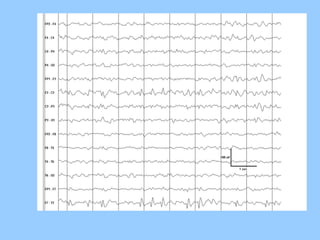

1. The document discusses EEG patterns and findings in various neurological conditions seen in children. It includes descriptions of normal EEG findings as well as abnormal patterns seen in conditions like absence seizures, West syndrome, benign childhood epilepsy with centrotemporal spikes, Lennox-Gastaut syndrome, non-convulsive status epilepticus, subacute sclerosing panencephalitis, and herpes encephalitis.

2. Case studies are presented with clinical histories and EEG findings to illustrate different pathologies. Treatment options are also mentioned for many of the conditions.